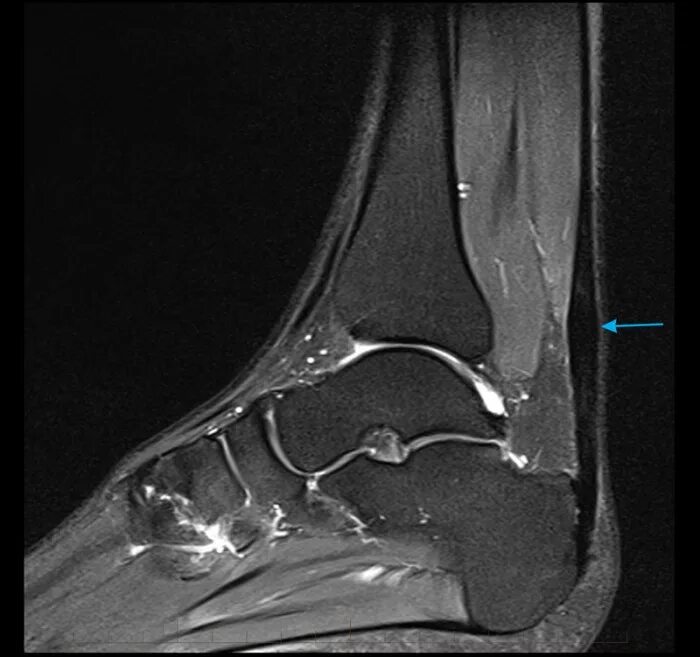

Мрт ахиллового сухожилия